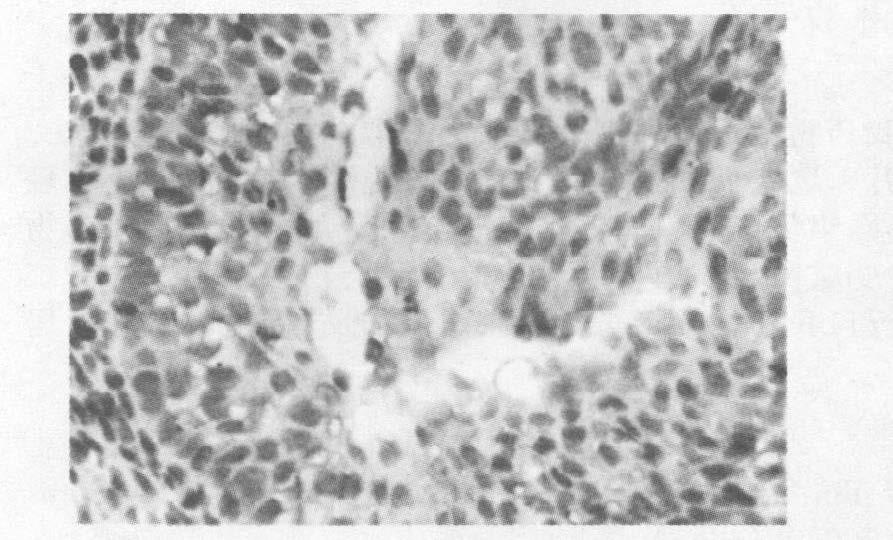

2.2 免疫组化指标检测 2.2.1 GD 20 EGF在生殖结节间充质细胞和尿道细胞中的表达(图 1~4)由图 1~4可见,在胚胎20 d,与对照组比较,染毒组EGFR在间充质细胞和尿道细胞中表达减弱。在间充质细胞和尿道细胞中EGF的表达,对照组灰度值分别为(93.74±2.0594) 和(100.184±0.66) ;染毒组依次为(110.533±2.679) 和(111.201±3.169 9) ;进行2样本均数的比较,差异有统计学意义(P<0.05) 。

图 1 对照组EGF 在间充质细胞中的阳性表达 |

图 2 染毒组EGF 在间充质细胞中的阴性表达 |

图 3 对照组EGF 在尿道细胞中的阳性表达 |

图 4 染毒组EGF 在尿道细胞中的阴性表达 |